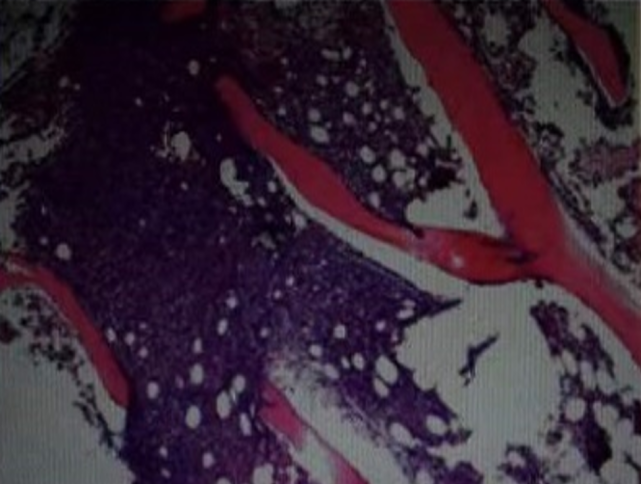

图片

胸膜活检病理见纤维脂肪组织内散在多量淋巴细胞,以B淋巴细胞为主,伴细胞明显挤压变形↑

5、胸腔镜病理结果:肉眼所见(右侧壁层胸膜)灰红色碎组织一堆,合计直径0.6cm。病理诊断意见:(右侧壁层胸膜)少量活检组织:纤维脂肪组织内散在多量淋巴细胞,以B淋巴细胞为主,伴细胞明显挤压变形。注:请结合临床进一步除外淋巴造血系统病变可能,必要时再取组织送病检。免疫组化:S2226808:CD3(少量+),CD20(2+),CD56(-),CKpan(上皮+),Ki-67(10%+)。